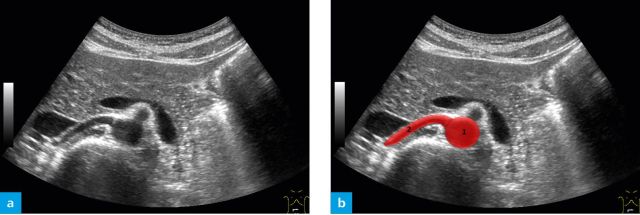

Ultrasound images are in grey-scale, with the intensity of each pixel approximately representing the amount of ultrasound reflected back from that point in space. Hence fluid is black (no reflection as the wave passes through), muscle is grey (some reflection from scattering as the ultrasound wave passes through) and the boarders between tissues are white (large reflections at these junctions).

Note the speckling pattern seen across all tissues and the clear differences in tissues between Rectus Abdominis and the surrounding fat.